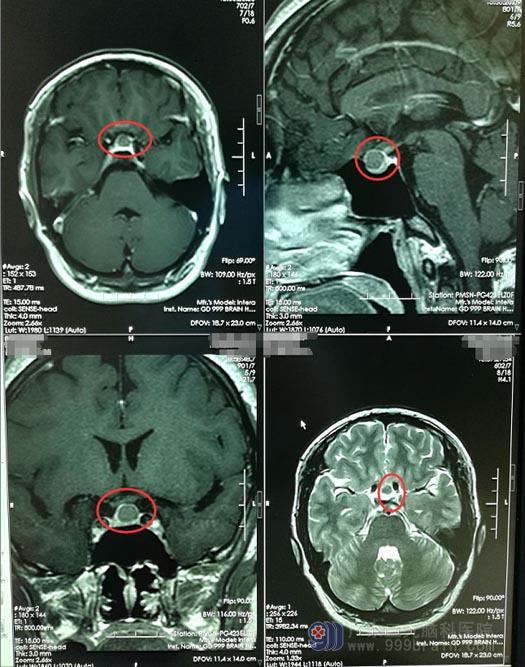

小玲2年前经历了二尖瓣膜置换术,不久后出现了头痛,呈阵发性,伴有视力下降,以左眼为主。在当地医院就诊,颅脑核磁共振检查提示鞍区占位。小玲刚刚经历了一次磨难,再加上手术后一直在服抗凝药,老公担心她耐受不了开颅手术,所以拒绝了进一步的治疗。

入院后,进一步脑部磁共振检查后,主管医生邓心情告诉小玲:鞍区占位,需要手术治疗,可以经鼻微创。